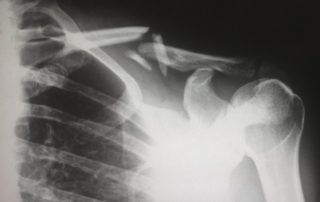

Using PRP for Treating Shoulder Injuries

Shoulder injuries can be a nuisance. Resulting from damaged tendons, muscles, cartilage and bones of the shoulder, these aren’t just painful but also result in loss of strength and flexibility. Usually, the way to go about shoulder injury treatment was through physiotherapy, or, in extreme cases, surgery. However, this doesn’t have to be the case anymore. With platelet rich plasma injections, you can now get a non-surgical treatment for many shoulder injuries that may not be responding to physiotherapy that is quicker and easier, than surgery, with far less [...]